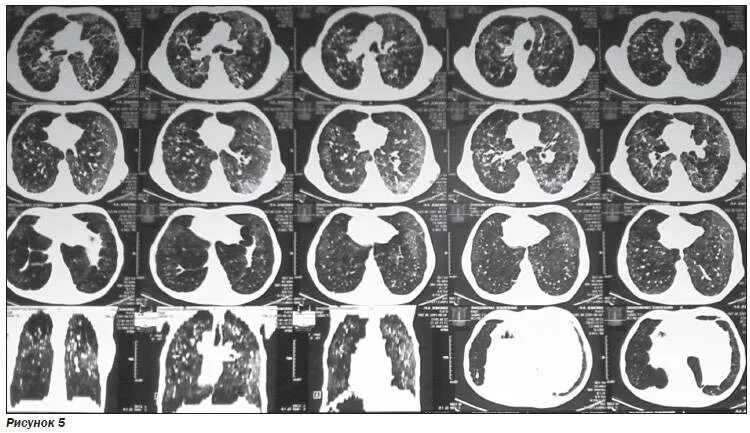

Метатуберкулезные изменения в легких что это означает